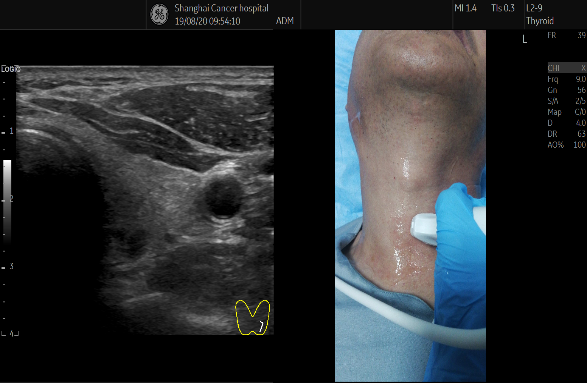

醫療設備